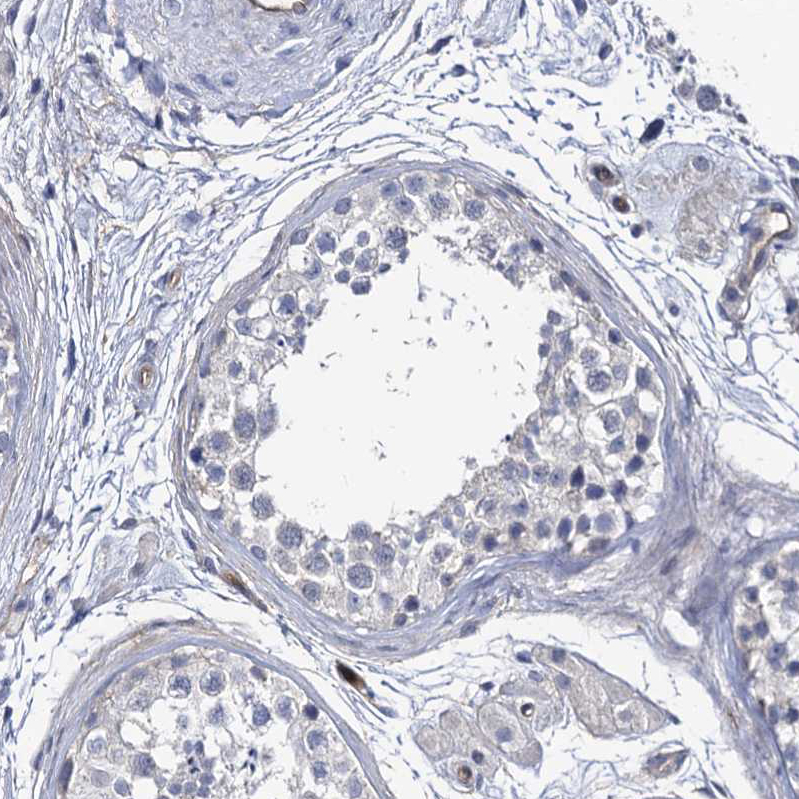

Immunohistochemical staining of human small intestine shows strong membranous positivity in glandular cells.